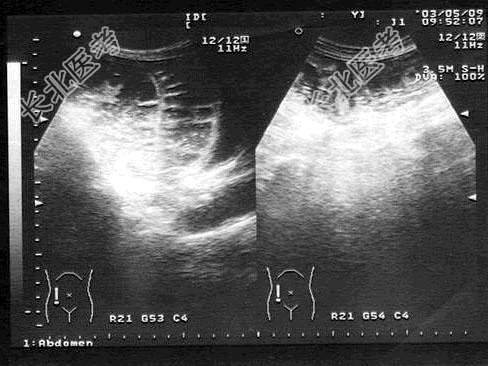

- 单项选择题男,6岁, 阵发性腹痛,呕吐数小时就诊。PE: 肠鸣音亢进,呈气过水音。根据超声检查如图, 诊断为

A、肠套叠

E、急性肠梗阻